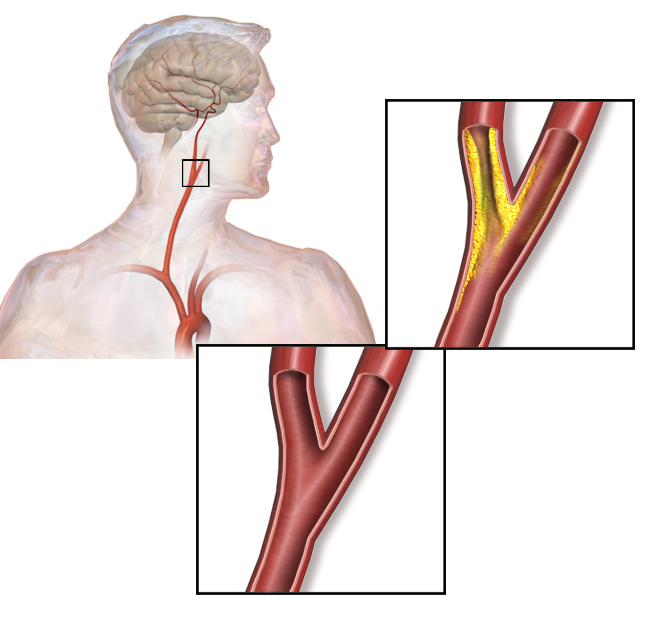

Overview

Package includes:

Days in hospital : 3 to 4 Days (For patient and one attendant)

Days in hotel : 8 Days (For patient and one attendant)

Room type in hospital : Shared

Room type in hotel : Private

Hotel category: Standard

Value added benefits of the Minimally Invasive Surgery with Carotid Endarterectomy:

Ø Doctor consultation charges

Ø Lab tests and diagnostic charges

Ø Room charges inside hospital during the procedure

Ø Surgeon Fee

Ø Nursing charges

Ø Hospital surgery suite charges

Ø Anesthesia charges

Ø Routine medicines and routine consumables (bandages, dressings etc.)

Ø Food and Beverages inside hospital stay for patient and one attendant.

Overview

Package includes:

Days in hospital : 4 to 5 Days (For patient and one attendant)

Days in hotel : 8 Days (For patient and one attendant)

Room type in hospital : Shared

Room type in hotel : Private

Hotel category: Standard

Value added benefits of the Vertebral Angioplasty:

Ø Doctor consultation charges

Ø Lab tests and diagnostic charges

Ø Room charges inside hospital during the procedure

Ø Surgeon Fee

Ø Nursing charges

Ø Hospital surgery suite charges

Ø Anesthesia charges

Ø Routine medicines and routine consumables (bandages, dressings etc.)

Ø Food and Beverages inside hospital stay for patient and one attendant.